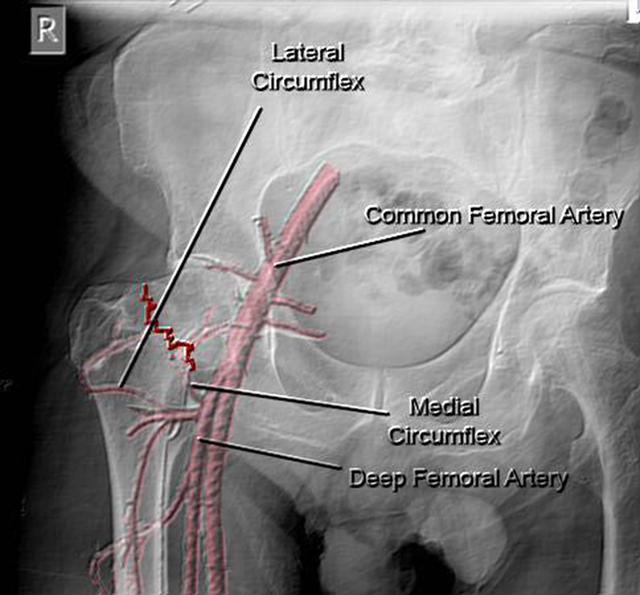

但是在股骨头这个区域呢,相对来讲血运就比较特殊了,这也就是股骨头区特别容易坏死的原因。供应股骨头区的血液可以分为从头部圆韧带过来的,还有从股骨颈部过来的血管。圆韧带过来的血管相对来讲,所支配的区域很有限,只有头部一小块的区域,头部其他区域的血供主要是靠颈部的血管来供应,但是颈部的血管呢,就特别的细,而且这股劲,一旦发生骨折以后发生错位,就会使得血管发生断裂的可能。从而造成股骨头部大部分的区域血供出现问题,而且这个区域侧支循环又很难以形成,久而久之就形成了骨坏死。